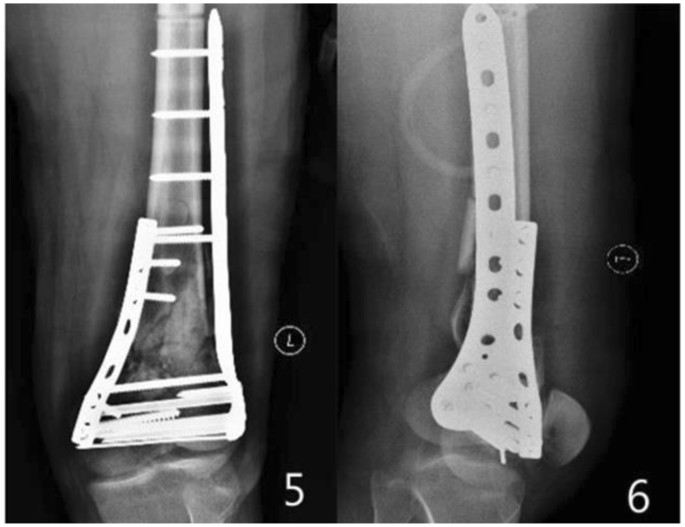

All patients were followed up for 12 to 48 months. The follow-up records of one patient of the double-plate group are shown in Figs 1–5 and those of one patient of the single plate group are shown in Figs 6 and 7. One patient in each group died one year and a half after the operation due to other causes. There were 58 patients and 60 cases of distal femoral fractures in total, of which one patient had bilateral distal femoral fractures both fixed by lateral plate and the other one with bilateral distal femoral fractures had a single plate on the right distal femur and double plates on the left. The age distribution of patients in the single-plate group and the double-plate group is shown in Table 1. There was no significant difference between the two groups (p = 0.330).

Single-plate group: The anterior lateral incision of femur was made and the fracture sites were exposed. The reduction of medial, lateral condyles, intercondylar and supracondylar fractures were performed one by one and Kirschner wires were used for temporary fixation. One stage bone grafting was performed for bone defects more than 1 cm. The lock plate with aiming sight was set under the muscle along the surface of the femur. After the temporary fixation on the distal end with Kirschner wire, guide pin was drilled into the proximal end of the fracture sites to keep the positions of fractures and plate. Assisted by x-ray examination of the fracture sites during operation, the screws were implanted correctly and kept away from the articular cavity. Then stability of the knee was evaluated by anterior and posterior draft test and stress test. If the varus stress test turned out positive and rupture of the lateral collateral ligament was excluded, the medial plate was set. Finally, we washed the wound, placed a negative pressure drainage tube, closed the incision layer by layer, and bandaged the leg up with an elastic bandage.

Double plates group: The lateral plate was set as the single-plate group. When setting the medial plate, the arcuate incision in the medial side of leg was made. Separated by layer by layer, the inferior segment of the femur was revealed while the vastus medialis were retained. Then the medial plate was implanted, fixed by no less than two screws on the distal fracture site. Finally, the knee varus stress test turned into negative.